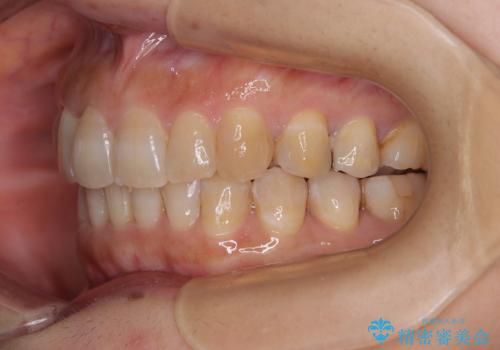

ディープバイトと前歯のデコボコ インビザラインによる矯正治療

- 前歯のディープバイトと叢生を気にして来院された患者様です。

目立ちにくい装置を希望されていたため、ワイヤー装置とインビザラインを提案したところ、インビザラインを希望されました。

下顎大臼歯が手前に倒れていたため、起き上がらせることで咬み合わせ高さを挙上し、ディープバイトと叢生を改善することとしました。

インビザライン特有の奥歯の噛みにくさが治療後半に発言しましたが、無事に終了させることができました。